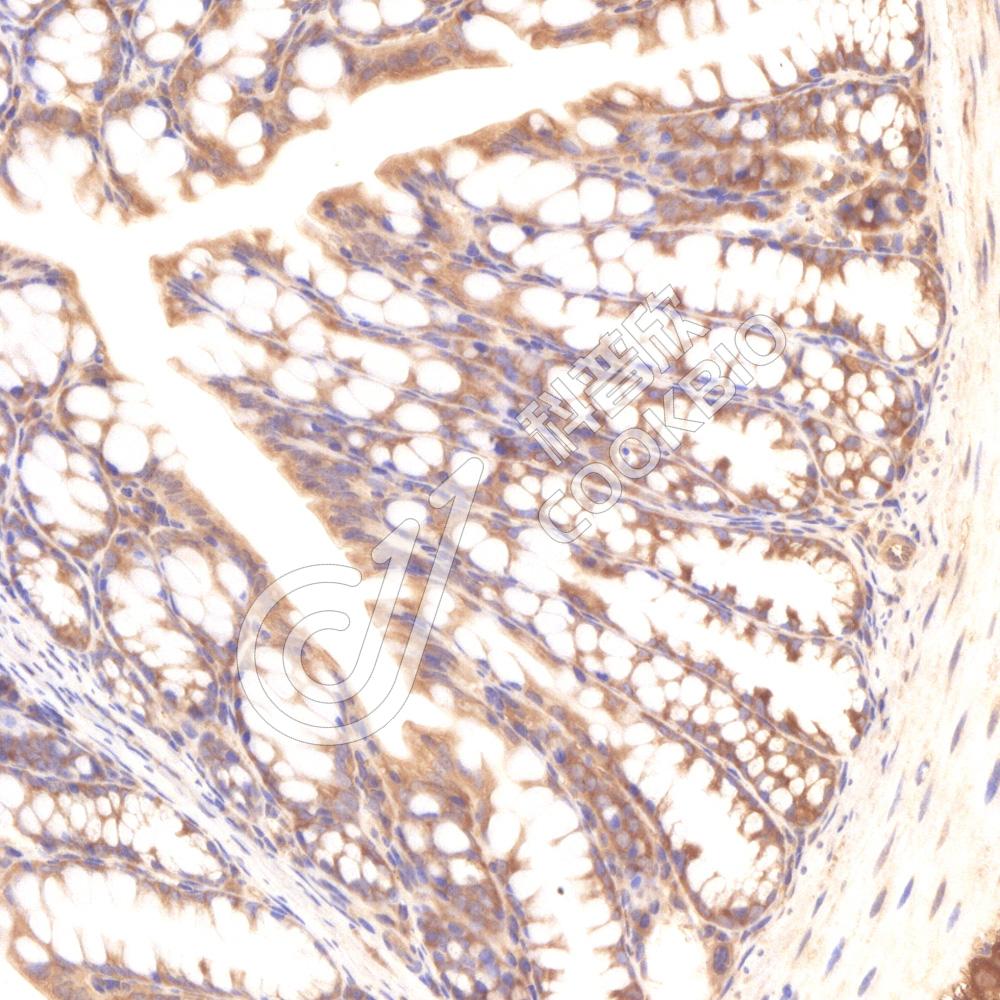

IHC检测RRAGB蛋白(货号 K1339126).

样品: 小鼠结肠, 4%多聚甲醛 (货号KSG1101) 固定12-24小时.

抗原修复: 柠檬酸抗原修复液(干粉, pH 6.0) (KSG1201), 98℃, 20分钟.

—抗: 1: 3000稀释, 4℃ 孵育过夜.

二抗: S-vision免疫组化多聚二抗(山羊抗兔),即用型 (货号KB3906), 室温孵育20分钟.